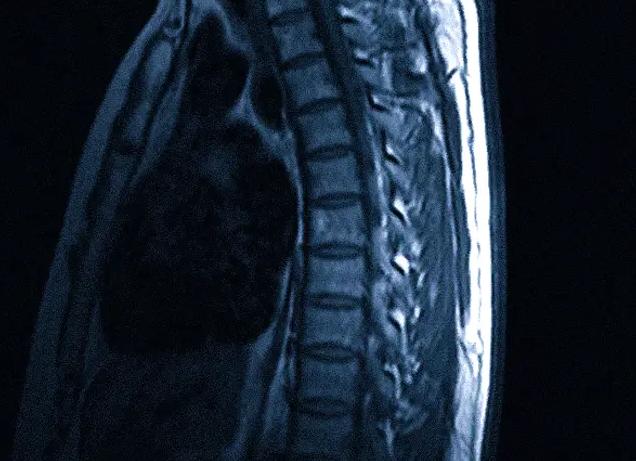

Магнитно-резонансная томография (МРТ) — один из молодых методов диагностики серьёзных патологий. Невзирая на факт высокой информативности и безопасности обследования, многие пациенты всё же сомневаются перед прохождением сканирования. Вредна ли МРТ? Актуальность этого вопроса сохраняется и по сегодняшний день.